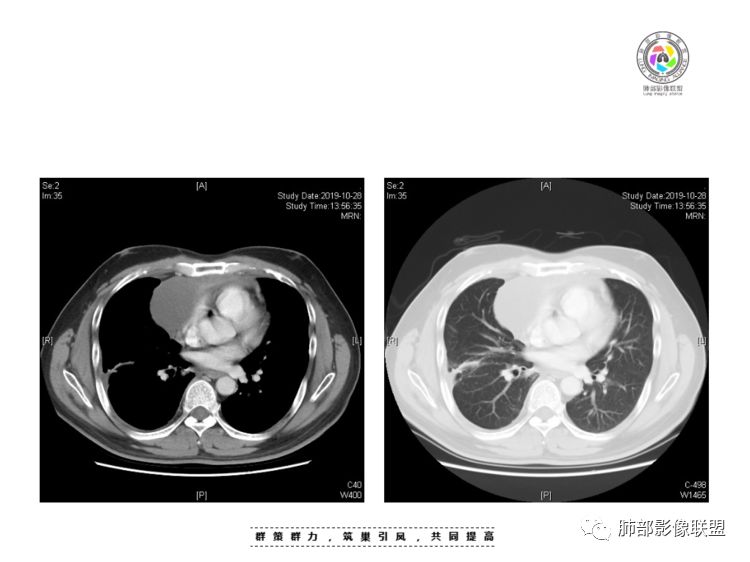

穿越七海的风:右前纵隔占位,恶性肿瘤,生殖来源?右肺实变是占位or肺不张?考虑为部分肺不张FeNo:右前纵隔占位,右肺结节,胸膜凹陷,小尾巴,右肺不张,考虑恶性杨旭华:恶性,前纵隔肿物,与血管关系密切,上腔静脉变窄,右肺野一元论考虑叶间裂增厚,恶性胸膜间皮瘤可能大小丽:到底是纵隔来源还是胸膜来源?我怎么倾向于胸膜来源,和叶间胸膜关系密切,而且纵隔内上腔静脉是向内侧推移。胸膜肿瘤(间皮瘤?SFT?)包裹性胸腔积液?马春平(张家港市一院胸外科):前纵隔占位,左无名受压,右大量胸腔积液可能是胸导管汇入处侵犯受压,考虑纵隔鳞癌孙冰伟:右上纵隔占位,也感觉和叶间胸膜关系密切,右侧胸膜局限性增厚,考虑恶性可能性大灵:前纵隔占位,血性胸水,胸膜凹凸不平,查见肿瘤细胞,结合免疫组化考虑胸腺癌。鉴别胸膜间皮瘤。采莲:右前上纵膈旁可见类圆形肿块,纵隔血管内移,感觉来源于胸膜,肿块内密度低,似水样密度,右侧胸膜广泛增厚,少量胸腔积液。心包少量积液。考虑胸膜间皮瘤,鉴别肺癌并胸膜转移?水晶石头:患者中年男性,胸闷15天。有“高血压、慢性肾小球肾炎”病史。查肿瘤标志物正常,胸水提示渗出液,胸水病理查见瘤细胞。胸部CT:右肺上叶后段结节、斑片影,见胸膜牵拉、包裹积液及部分纤维条索灶,似见卫星灶,右侧胸膜增厚。前纵隔脂肪密度增厚,右侧可见类圆形低密度(液体)肿块,边缘光滑。综合考虑右肺腺癌并胸膜转移,结核可能。周太狼:考虑纵隔胸膜来源肿瘤,恶性,胸膜间皮瘤伴转移?徐飞:中年男性,影像为右侧胸腔及叶间积液,叶间胸膜增厚轻度强化。前纵隔右侧心缘旁团块,可见坏死。胸水见癌细胞,综合考虑恶性,胸腺癌伴转移。小赵:中年男性,血性胸水,常规查见癌细胞,李凡他实验阳性。胸部CT示前纵隔见不均匀密度影,与邻近大血管分界不清,囊变坏死明显,增强扫描呈不均匀强化,心包及右侧胸膜增厚,并心包及右侧胸腔少量积液。综合考虑胸腺癌。右肺中叶病变周围见多发纤维条索,支气管部分进入病灶,考虑炎性病变。流心明智:患者,男性,50岁。胸闷15天。高血压20年,慢性肾小球肾炎15年。肿标正常,胸水提示渗出液,胸水查见癌细胞。胸部CT:右肺肿块影,斑片影,索条影,可见胸膜牵拉、多发包裹积液,纵隔上腔静脉受累,心包受累。综合考虑:ROSE似腺?考虑右肺腺癌并胸膜转移,心包受累。鉴别胸腺Ca、淋巴瘤,纵隔病变不懂,等老师们精彩分析。王秀仙:前纵膈囊实性肿块,与纵膈分界不清,心脏大血管及上腔静脉受压向内后移,右侧后胸膜、侧胸膜增厚,右侧叶间裂不规则增厚,心包积液,根据腔静脉移位情况,考虑纵膈胸膜来源恶性肿瘤,胸膜间皮瘤?鉴别胸腺癌并胸膜转移。高广飞:上纵隔占位,右侧叶间胸腔积液,需考虑恶性自信人生:多发囊实性病灶,包裹性积液,考虑胸膜来源 只是没有看到壁结节,恶性胸膜间皮瘤巴伟:前上纵隔占位,胸膜及心包结节,考虑胸腺瘤或癌,右肺病灶,先考虑陈旧炎性病变。Lenle董:前纵隔占位,部分边缘模糊,病灶内囊变?坏死?上腔静脉受侵,考虑胸腺癌;叶间片状影,强化明显,炎性考虑。常志强:前纵隔囊实混杂密度肿块,边界不清,实性部分强化明显,结合胸水内见癌细胞,考虑恶性肿瘤伴转移。飞鹰行动:前纵隔占位,软组织密度及囊性密度,实性部分密度均匀,致密,病灶与周围血管分界不清,增强后病灶强化有类似不温不火强化,部分血管受侵犯,右肺见肿块样病变及条索状病变,一元论,考虑淋巴瘤,二元论,考虑胸腺瘤B2—B3伴右肺病变。尽量一元论考虑,淋巴瘤可能。看图说话:右肺索条病灶,边缘膨隆,胸膜牵拉,考虑右肺癌伴胸膜转移。晨:前纵隔囊实性肿块,与纵隔分界不清,右侧后胸膜、侧胸膜增厚,右侧叶间裂不规则增厚,考虑纵隔胸膜来源恶性肿瘤,考虑胸腺癌并胸膜转移。丽:中年男性,前纵隔囊实性肿块,呈偏心性生长,临近大血管受压推移,增强后实性部分不均匀强化,心包可见条形积液,考虑胸膜来源恶性肿瘤,胸腺癌可能大。另右肺多发斑片状高密度影及实变密度影,实变影呈均匀强化,右侧胸膜局限性增厚,考虑炎性病变。小飞:右前纵隔囊实性占位,实性部分明显强化,右侧叶间胸膜增厚,右侧胸腔积液,心包积液,考虑恶性胸腺瘤!尘缘:支持恶性胸腺瘤(囊实性肿块,实性强化,且侵犯纵隔,脂肪间隙模糊)伴肺内及胸膜转移。浪迹天涯:考虑侵袭性胸腺瘤——胸腺前纵隔占位,周围脂肪间隙模糊不清。尘缘:不除外另一种可能:二元,肺内腺癌合并胸膜转移,纵隔的畸胎瘤可能。一米阳光:晨读中年男性,右肺结节影,叶间裂及胸膜增厚牵拉,右侧胸水。心包多发结节改变。胸水查见癌细胞。考虑,腺癌并转移。鉴别,胸膜间皮瘤并转移前纵隔囊实性占位,二元考虑。心灵鸡汤:老年男性,右肺中叶外段长条状软组织密度影,边缘膨隆,邻近胸膜牵拉,部分胸膜有栽脏,右中叶外侧段支气管堵塞,常规考虑恶性肿瘤,腺癌可能,结核、鳞癌不除外,另右肺上叶斑片影,小叶性肺不张?右前纵隔囊实性不规则形密度影,其内见部分脂肪样极低密度影,与邻近血管边界不清,心包外膜有侵犯,增强未见纵隔窗平扫,实性及分隔见增化,其内低密度影未强化,考虑低度恶性纵隔肿瘤,间皮瘤可能,畸胎瘤、淋巴瘤待排,建议支气管镜及穿刺活检。曹志勇:右前纵隔考虑来源于胸膜的恶性肿瘤,右肺内病灶考虑鳞癌,二元德芙~云味:中年男性,右肺见结节、斑片影,右侧包裹积液、胸膜牵拉,纤维条索,前纵隔囊性占位,考虑腺癌、并转移。欧阳英:右前中纵隔囊实性肿块及右肺内结节灶,支持恶性肿瘤,胸腺癌并肺内转移可能张延军:前纵隔见不规则软组织影,密度不均,右侧缘见囊变区,纵膈及侧胸壁胸膜增厚,增强呈不均匀强化,右肺中叶见结节灶,近段支气管阻塞,叶间胸膜不规则增厚,考虑1:右肺中叶腺癌伴纵膈及胸膜转移;2:前纵膈侵袭性胸腺瘤并胸膜侵犯,中叶炎性改变?彭君:老年,前纵隔占位 ,坏死边缘清, 侵犯心包 右侧胸膜及叶间胸膜结节 ,少量胸水, cea不高 ,考虑恶性, 间皮瘤可能 ,转移待除外。毛勤香:恶性没问题,胸水查见癌细胞,一元还是2元,右肺中叶肿块,边缘毛糙,局部似有毛刺,周围有粘连,右侧胸膜腔少量积液,胸膜增厚多发结节,含叶间裂结节,纵膈脂肪间隙模糊,纵膈胸膜增厚,心包增厚积液,右前那个类圆形低密度肿块,纵膈血管内移,我考虑胸膜来源可能性大,综合考虑,一元肺腺癌并多发转移,二元考虑胸膜间皮瘤并多发转移,肺内炎症不张。

本例纵隔与肺内两处病变,回顾总结分析:

2、前纵隔内病灶囊实性混杂密度病灶,囊性病灶主要位于右侧,张力较高,有分隔影,囊壁右侧缘光整,病灶左侧实性部分边界不清明显强化,病灶肺瘤交界面大部分边界清楚,部分模糊。

前纵隔肿块伴囊变坏死常见以有胸腺瘤、胸腺癌、淋巴瘤和生殖细胞肿瘤。

纵隔内病灶不符合肺癌转移途径,且纵隔内单发的囊实性转移罕见。淋巴瘤无论是分布、形态、密度、还是强化方式度不符合。

胸腺瘤/胸腺癌:病灶内那么大的囊,常规考虑B型以上胸腺瘤,囊内有分隔影,病灶周围脂肪间隙模糊,常规考虑侵袭性胸腺瘤或胸腺癌,若侵袭性胸腺瘤,常侵犯胸膜、心包,很少累及肺。胸腺癌易侵犯胸膜、肺并纵隔淋巴结及远处转移。但肺内腺癌形态更符合原发灶。胸膜及叶间裂转移则即可来自肺,也可来自胸腺癌。